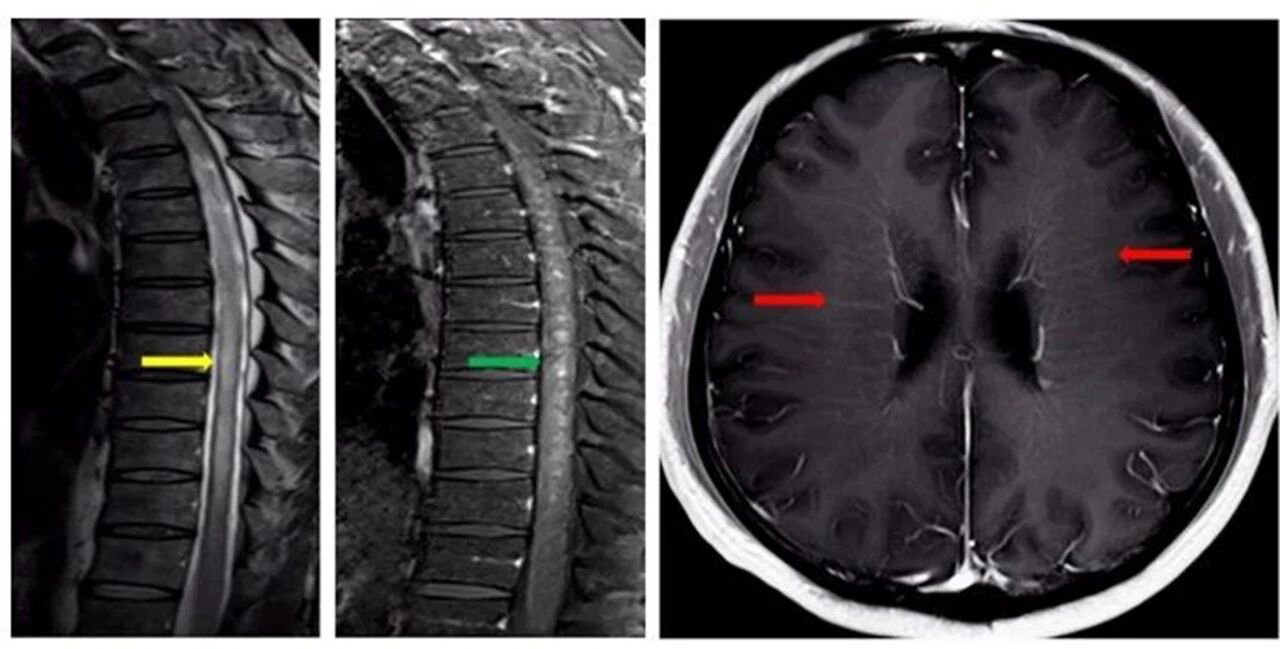

万分焦虑之下,陈老师慕名找到了南京市第一医院神经内科主任医师、医学博士时建铨,在仔细梳理了陈老师病情后,时建铨认为对称性下肢无力、上肢感觉异常及排尿功能障碍这三个症状看似互不相关,但串联在一起则指向了同一个方向,可能存在脊髓方面问题。时建铨给陈老师安排了脊髓+头颅增强核磁共振检查,结果提示:脊髓长节段异常信号(图1中黄色箭头)伴斑片状强化(图1中绿色箭头),且脑室周围存在线样放射状强化(图1中红色箭头)。

根据影像学表现,结合陈老师不断加重的症状,符合亚急性进展性病程,经验丰富的时建铨脑海中顿时闪现出一种疾病——自身免疫性胶质纤维酸性蛋白(GFAP)星形胶质细胞病。时建铨又安排陈老师进行脑脊液检查,对其中抗GFAP抗体水平进行了检测。检测结果提示:陈老师脑脊液抗GFAP抗体为阳性,印证了之前的判断。

专家指出,该病典型影像学特征为头颅核磁共振检查显示脑室周围线样放射状强化;脊髓核磁共振检查显示颈胸段脊髓长节段异常信号伴斑片状强化。脑脊液抗 GFAP 抗体阳性是确诊的核心证据。